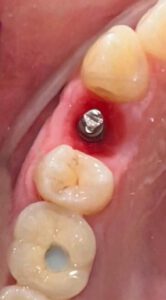

5. Caso real: Dientes nuevos en cuestión de horas

Muchos pacientes nos preguntan: “¿De verdad puedo cambiar mi boca en un solo día?”. La respuesta es sí. En casos bien indicados, integramos planificación, cirugía y prótesis fija provisional en una sola jornada.